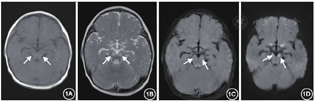

辅助检查(括号内为正常参考):血乳酸多次增高,波动在5.2~14.9 mmol/L(参考值0.5~2.2 mmol/L,以下同);血气分析示:酸碱度(pH)下降明显,波动在7.09~7.30(7.35~7.45)之间,碱剩余(BE)增高明显,波动在-21.5~-5 mmol/L(-4~2 mmol/L);碳酸氢根(HCO3-)16~20 mmol/L(22~27 mmol/L)提示呼吸性酸中毒合并代谢性酸中毒改变。肝酶+心肌酶+电解质提示:谷丙转氨酶(ALT)71.80 IU(0~40 IU),谷草转氨酶(ALT)98.40 IU(0~40 IU);肌酸激酶(CK)587.7 IU(40~190 IU),肌酸激酶同工酶(CK-MB)63.10 IU(0~50 IU),乳酸脱氢酶475 IU(0~450 IU),血清钾3.18 mmol/L(3.5~5.5 mmol/l),血钠139.30 mmol/L(135~145 mmol/L),其余正常。甲状腺功能八项:三碘甲状原氨酸(TT3)0.791 nmol/L(1.4~3.4 nmol/L),促甲状腺激素(TSH) 2.94 IU/ml(0.34~4.6 IU/ml);甲状腺素(TT4)42.05 nmol/L(76.6~189 nmol/L)偏低;游离T3(FT3)42.05 nmol/L(3.68~8.46 nmol/L),提示甲状腺功能低下,其余均正常。血氨、同型半胱氨酸及铜蓝蛋白正常;脑脊液常规、生化、乳酸、病原学检查、自身免疫性脑炎相关抗体检查:均未见异常;血尿串联质谱分析:未见异常。视频脑电图(VEEG):背景活动节律慢化,额、中央、颞区(右侧著)为主棘波稍多量发放。神经电图+肌电图:双上下肢体感通路检查潜伏期延长,波幅偏低。头颅MRI(病程第9天)提示双侧丘脑、大脑脚、脑干对称性片状稍长T2信号影(图1)。复查头颅MRI(病程第40天)提示:脑损伤,颅内部分异常信号较前显示增多,原有部分异常信号较前显示稍少,双侧脑室稍扩大;双侧大脑半球脑沟裂增宽加深,第三、第四脑室饱满(图2)。脊髓MRI平扫+增强未见明显异常。

硫辛酰基转移酶-1缺乏症患儿头颅影像学显示髓鞘形成延迟、双侧额叶白质异常和小脑萎缩,皮质萎缩,双侧丘脑、脑干、基底节等对称性异常等常见。有报道的5例起病患儿中例1及例5有脑萎缩、发育延迟,侧脑室扩张;丘脑异常信号;例1及例5患儿头颅磁共振波幅(MRS)可见乳酸峰,同时监测血乳酸升高,该现象可能与谷氨酰胺、脯氨酸升高神经毒性作用于线粒体导致能量供应障碍有关[8, 16]。本例起病年龄较晚,头颅影像学提示脑干、丘脑受累显著,未查头颅磁共振波普检测乳酸峰累积状况,结合本例治疗后复查头颅MRI提示多部位有进展,受累较前加重,脑萎缩明显,与硫辛酰基转移酶-1缺乏症经典头颅MRI改变不完全相符,提示生活质量欠佳及预后总体不良,可继续随访观察临床转归及影像学改变。